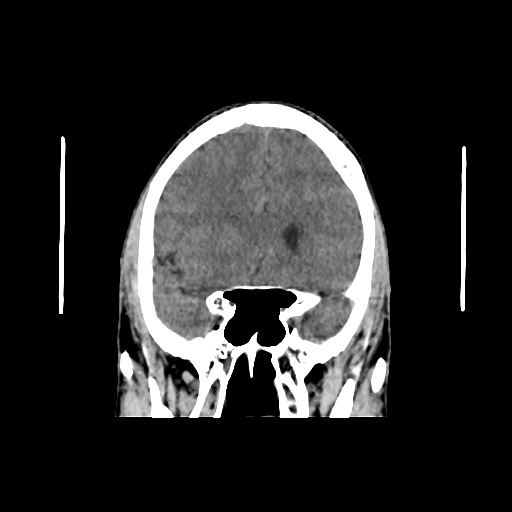

CT scan of brain images: